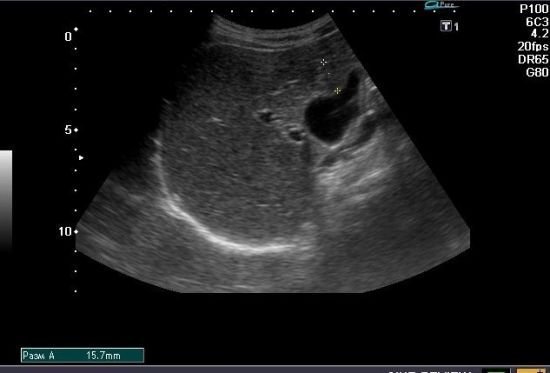

- УЗД печінки